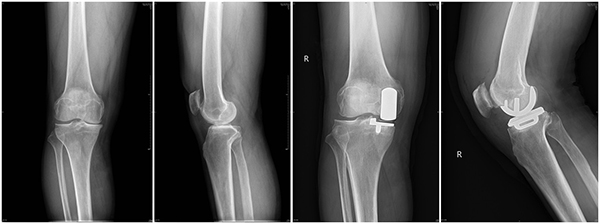

徐醫(yī)附院骨關(guān)節(jié)科成功開(kāi)展首例全生物型牛津單髁膝關(guān)節(jié)置換術(shù)

黃淮網(wǎng)  近日,在院領(lǐng)導(dǎo)的關(guān)心和支持下,在骨關(guān)節(jié)科、手術(shù)室的配合下,徐州醫(yī)科大學(xué)附屬醫(yī)院骨關(guān)節(jié)科盧文海、史思峰及孫少松醫(yī)師成功為一位膝關(guān)節(jié)骨性關(guān)節(jié)炎患者實(shí)施了全生物型牛津單髁膝關(guān)節(jié)置換術(shù)。該手術(shù)為膝關(guān)節(jié)單髁置換手術(shù)中的一種新的方式,為徐醫(yī)附院首次采用,為該院骨關(guān)節(jié)科在膝關(guān)節(jié)單髁置換技術(shù)方面又增加了一項(xiàng)新的內(nèi)容。

來(lái)自安徽宿州的患者王先生,因?yàn)橄リP(guān)節(jié)疼痛3余年、加重1年入院,診斷為“右膝關(guān)節(jié)骨性關(guān)節(jié)炎”,患者右側(cè)膝關(guān)節(jié)內(nèi)翻畸形,內(nèi)側(cè)間隙疼痛明顯,無(wú)法自主蹲起及長(zhǎng)距離行走。經(jīng)骨關(guān)節(jié)科醫(yī)師討論認(rèn)為:患者病痛位于膝關(guān)節(jié)內(nèi)側(cè),內(nèi)側(cè)間室的軟骨破壞明顯,具備內(nèi)側(cè)單髁置換手術(shù)指征,無(wú)手術(shù)禁忌癥,于2021年7月15日在盧文海副主任醫(yī)師、史思峰副主任醫(yī)師、孫少松主治醫(yī)師協(xié)作配合下進(jìn)行了右膝關(guān)節(jié)內(nèi)側(cè)全生物型單髁置換術(shù)。手術(shù)順利。術(shù)后第二天患者即可自行下地行走,術(shù)后功能恢復(fù)良好。7月20日,王先生出院。8月27日,他來(lái)院復(fù)查時(shí),自己行走自如,屈伸活動(dòng)良好。

盧文海副主任醫(yī)師介紹,膝關(guān)節(jié)單髁置換相對(duì)于全膝關(guān)節(jié)置換而言是一種微創(chuàng)術(shù)式。只對(duì)膝關(guān)節(jié)內(nèi)側(cè)或外側(cè)間室進(jìn)行表面置換,不需要去除膝關(guān)節(jié)內(nèi)的前后交叉韌帶,最大限度的保留了患者的本體感覺(jué)和關(guān)節(jié)功能,具有創(chuàng)傷小、疼痛輕、恢復(fù)快的優(yōu)點(diǎn)。而生物型牛津單髁膝關(guān)節(jié)置換術(shù)(Cementless Oxford Unicompartmental Knee Arthroplasty,COUKA)自2004 年由牛津大學(xué)首創(chuàng)以來(lái),國(guó)外臨床應(yīng)用較多,但在國(guó)內(nèi)起步較晚。使用生物型牛津單髁膝關(guān)節(jié)假體可避免骨水泥相關(guān)并發(fā)癥,縮短手術(shù)時(shí)間;減少透亮線,以期望降低翻修率。不過(guò)生物型牛津單髁假體的使用要嚴(yán)格掌握適應(yīng)癥,對(duì)于骨質(zhì)疏松、局部骨壞死、術(shù)后活動(dòng)較大、髁畸形等患者要慎重選擇。